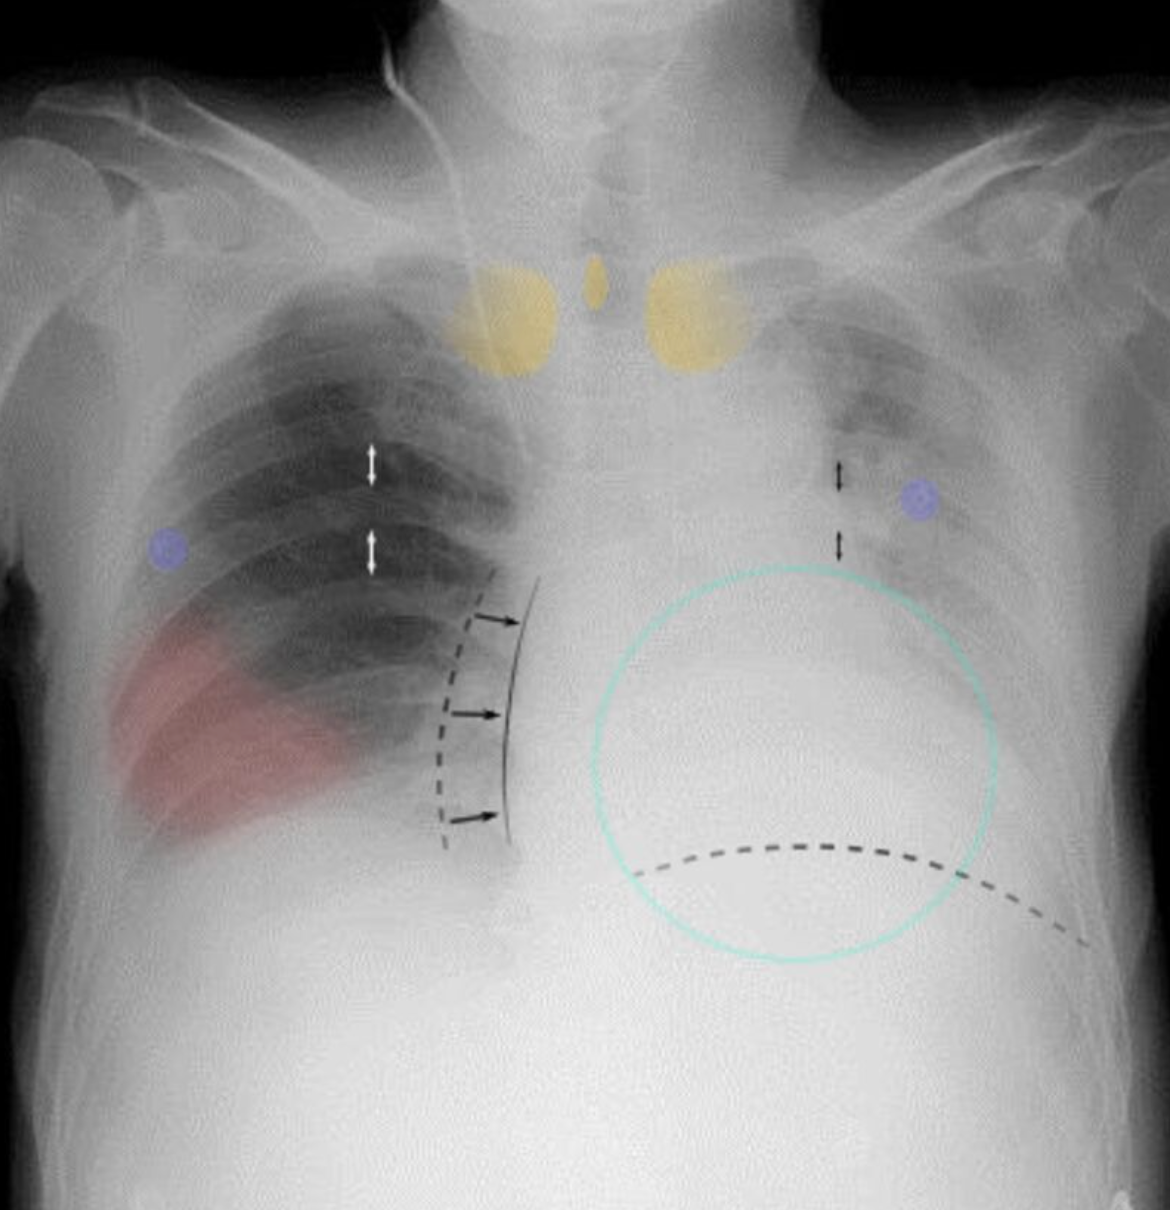

Atélectasie

++ à 72h postop

1. Clinique

2. Diag :

1. Gazo Aa

→ hypoxémie, ± PaCO2 faible et alcalose

2. Rx

1. collapsus lobaire → opacification homogène

2. Shift médiastinale coté ipsi

3. TTT

• Mobilisation précoce

• Manœuvres d’expansion pulmonaire → ⇡ pression+ en fin d’expiration

• Traitement de la condition sous-jacente

4. Prévention post chir → prescrivant opioïdes soulager la douleur → prudence car suppression de la toux